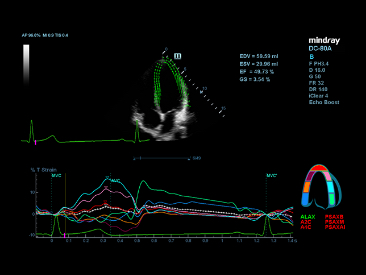

eXceptional intelligence

Intelligenz entlang des gesamten Workflow

Um die Scaneffizienz genauer und konsistenter zu machen, bietet X-Insight eXceptional intelligence w?hrend des gesamten Untersuchungsablaufs, von der Ebenenerfassung bis zur Bildoptimierung und von der Berechnung bis zum Untersuchungsprotokoll.